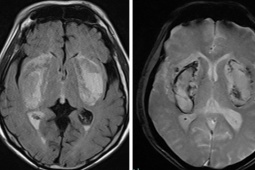

Ảnh minh họa